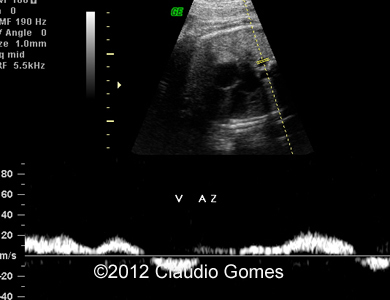

Image 2: Routine transverse view of the abdomen and thorax showing a vessel posterior and to the right of the aorta (Azygos vein).

Fig3